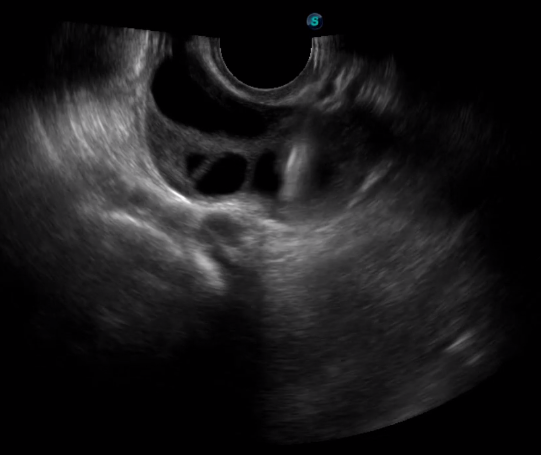

TEE(經(jīng)食道超聲心動圖)將超聲探頭置入食道內(nèi),從心臟的后方向前近距離探查其結(jié)構(gòu) ,克服了經(jīng)胸超聲檢查的局限性,避免肺內(nèi)氣體、胸壁脂肪、胸廓畸形等因素影響,觀察角度更多,圖像更加清晰,測量數(shù)據(jù)更準(zhǔn)確。

經(jīng)食道超聲 大動脈短軸